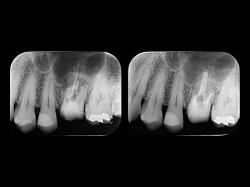

写真の歯は短い歯の根の周りに膿がたまっていて、長い歯根は先端が大きく削られていて充填材が飛び出しています。

抜歯の前日に当院を受診され、抜かずに残す治療を行うことになりました。

短い歯根は外科的に取り除き(歯根端切除)、長い歯根は充填材を取り除いて特殊な接着剤(MTA)で封鎖しました。

MTAセメントは従来の充填材料と比べて格段に生体になじみの良い材料ですので、

良好な治癒が期待できます。

現在ほぼ問題なく経過しています。